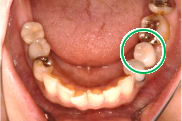

女性Kさん 70代(インプラント)

主訴

左下、ブリッジの支台になっていた奥のほうを抜歯したままになっている。ここのところを何とかしたい。

治療内容

ブリッジの奥に伸びていた部分を削り取り、インプラントを2本入れました。

所感

左下ブリッジのところを切り離し、奥を抜歯したままになっていました。このままでは、ブリッジの前方の支台になっていた歯に負担がかかり、将来抜歯になる可能性があることをお話ししました。歯がないところを補う方法には、部分入れ歯かインプラントがあることを説明すると、自分の歯と同じ感覚で食事ができるインプラントを選択されました。X-Guideを使用し埋入しました。口を大きく開けることができない方でしたので、X-Guideの長所のうちの一つを活かすことができました。

インプラント2本:¥363,000×2本=¥726,000(税込)

Before

青丸の部分を削り取りました

After